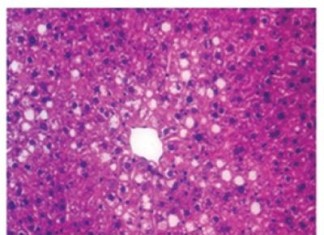

La grasa en el hígado recibe una llamada de atención que...

Un equipo de investigadores de Penn, dirigida por Mitchell Lazar, MD, PhD, director del Instituto de Diabetes, Obesidad y Metabolismo en la Facultad de...